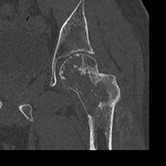

Musculoskeletal — Clear Cell Chondrosarcoma Joel Lim, MD |